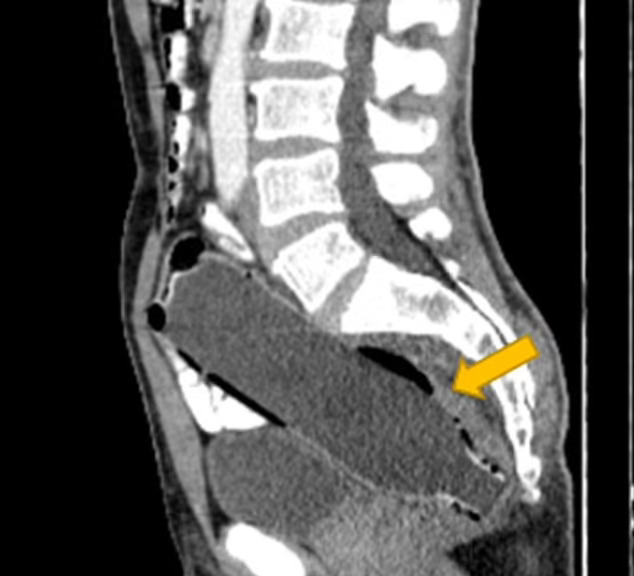

Тоа нормално било забележано кога бил испратен на КТ скен. Тие рекоа дека не сакал да открие дека го внел предметот во себе поради „срам и страв од неговата сопруга“.

Сепак на крајот им објаснил како го направил тоа, и мора да признаеме дека во сето ова има и некои логички потези. Прво го турнал дното на шишето, за после тоа да може да го извлече со фаќање за горниот дел. Но работите излегле од контрола и тој не можел да го извади предметот, оставајќи го пластичното шише длабоко во неговото дебело црево.

Мажот веднаш бил однесен на операција и анестезија за да го нокаутира и да му се опушти сфинктерот. Хирурзите потоа „внимателно и полека“ го извлекле шишето. Последователните тестови не откриле докази дека шишето му предизвикало внатрешни повреди или перфорација на долниот дел од цревата.